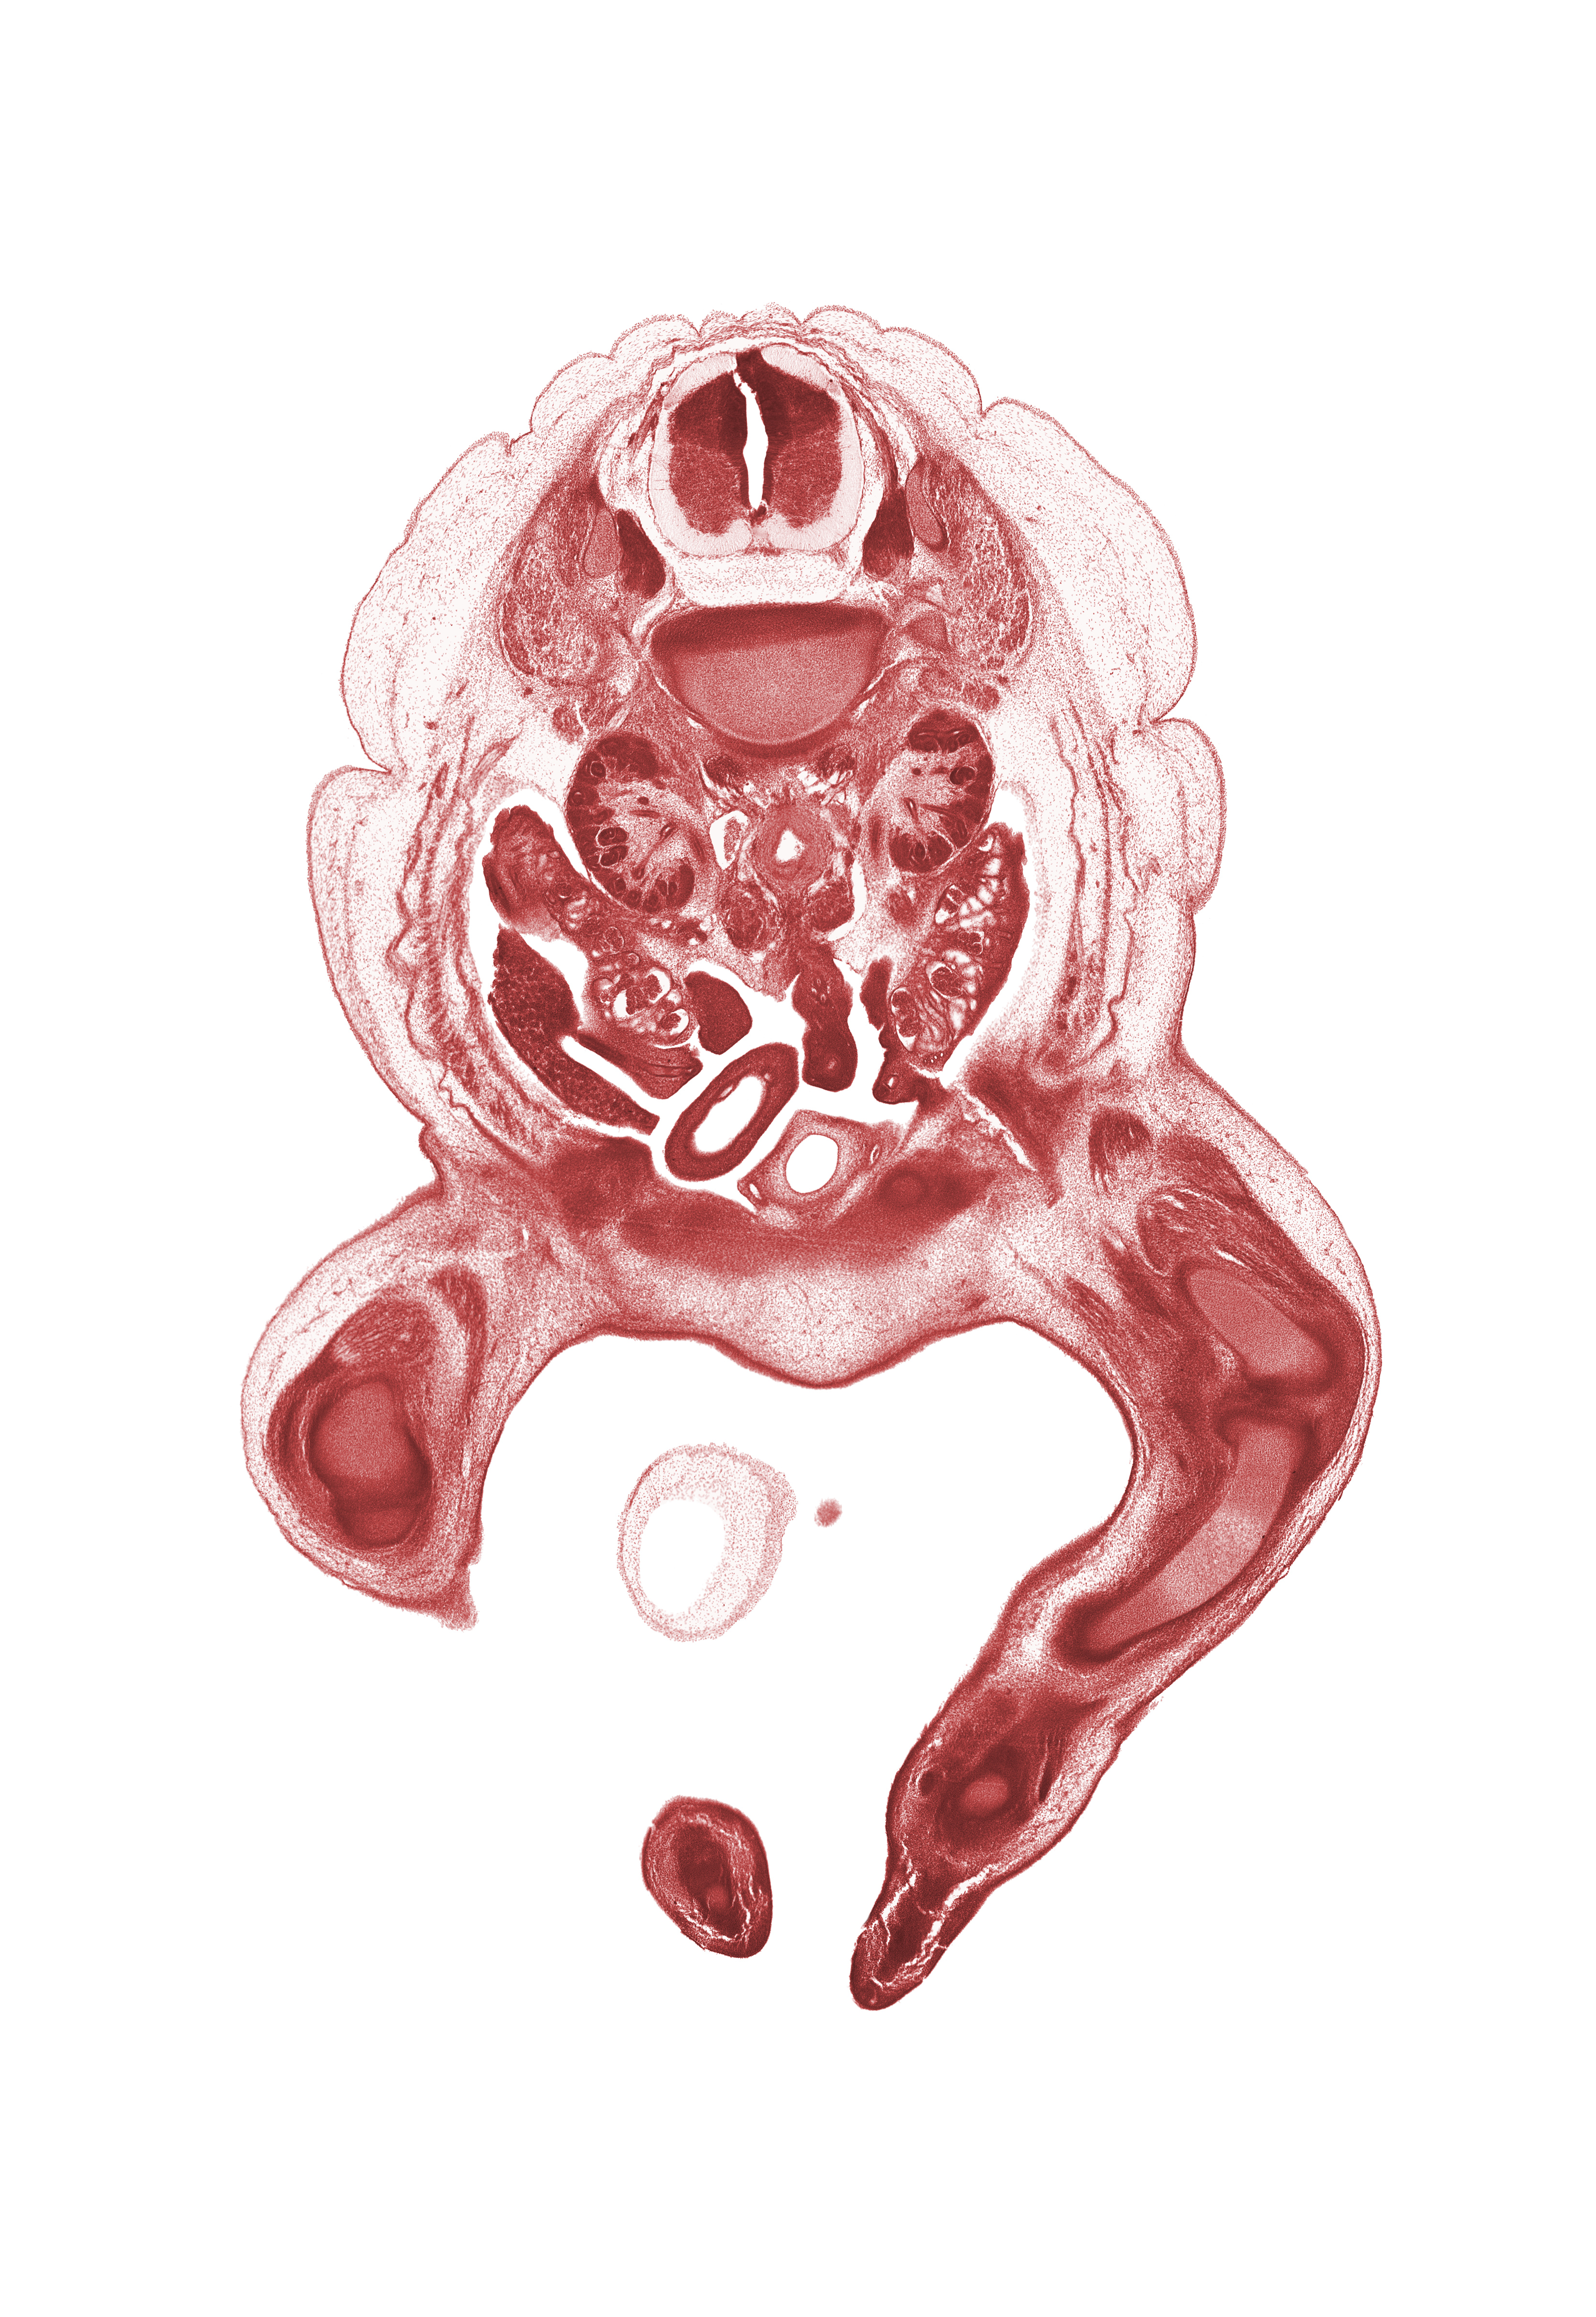

Carnegie Embryo #4090 | Location: 22-9

Keywords: L-1 spinal ganglion, L-1 spinal nerve, amnion on surface of umbilical cord, aorta, degenerating mesonephros, duodenum, gubernaculum of ovary, intermediate zone, kidney (metanephros), knee joint, marginal zone, paramesonephric duct, patellar ligament, pubis, quadriceps femoris muscle, right umbilical artery, subarachnoid space, sympathetic trunk, tibia, toe, toe of right foot, urinary bladder, ventricular zone

Source: The Virtual Human Embryo.